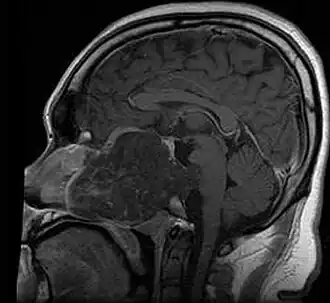

| MRI of extensive clival chordoma in 17-year-old male patient, axial view. Tumor in the nasopharynx extending from nasal cavity to brainstem posteriorly is clearly visible. | |

Chordoma is a rare slow-growing neoplasm (cancer) that arises from cellular remnants of the notochord in the bones of the skull base and spine. The evidence for the notochordal origin of chordoma is the location of the tumors (along the neuraxis), the similar immunohistochemical staining patterns, expression of brachyury, and the demonstration that notochordal cells are preferentially left behind in the clivus and sacrococcygeal regions when the remainder of the notochord regresses during fetal life.

In layman's terms, chordoma is a type of bone cancer, and is classified as a sarcoma.[1] Chordomas are sometimes mistakenly referred to as a brain, brainstem or spinal cord tumors due to their location near those critical structures, but they are not derived from nervous tissue.

Chordomas can arise from bone in the skull base and anywhere along the spine. The two most common locations are cranially at the clivus and in the sacrum at the bottom of the spine.[2] Very rarely, chordomas present outside of the skull base or spine; these are called extra axial chordomas.[3]

In most cases, complete surgical resection followed by radiation therapy offers the best chance of long-term control.[17] Incomplete resection of the primary tumor makes controlling the disease more difficult and increases the odds of recurrence. The decision whether complete or incomplete surgery should be performed primarily depends on the anatomical location of the tumor and its proximity to vital parts of the central nervous system.[18]

Chordomas are relatively radioresistant, requiring high doses of radiation to be controlled. The proximity of chordomas to vital neurological structures such as the brain stem and nerves limits the dose of radiation that can safely be delivered. Therefore, highly focused radiation such as proton therapy and carbon ion therapy are more effective than conventional x-ray radiation.[19]